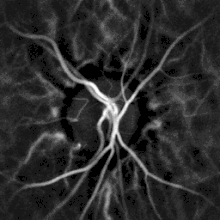

Remote, indirect monitoring of blood flow by laser Doppler

Noninvasive hemodynamic monitoring of eye fundus vessels can be performed by Laser Doppler holography, with near infrared light. The eye offers a unique opportunity for the non-invasive exploration of cardiovascular diseases. Laser Doppler imaging by digital holography can measure blood flow in the retina and choroid, whose Doppler responses exhibit a pulse-shaped profile with time[27][28] This technique enables non invasive functional microangiography by high-contrast measurement of Doppler responses from endoluminal blood flow profiles in vessels in the posterior segment of the eye. Differences in blood pressure drive the flow of blood throughout the circulation. The rate of mean blood flow depends on both blood pressure and the hemodynamic resistance to flow presented by the blood vessels.